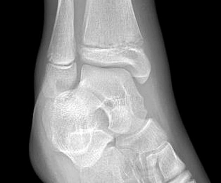

A 13-year-old girl sustains an ankle injury during a soccer match. Radiographs reveal an isolated Salter-Harris III fracture of the anterolateral distal tibial epiphysis (Tillaux fracture). Which of the following describes the anatomical sequence of distal tibial physeal closure that predisposes adolescents to this specific fracture pattern?

A 13-year-old female sustains a fracture of the anterolateral aspect of her distal tibial epiphysis after an external rotation injury. This fracture pattern (Tillaux fracture) occurs specifically due to the asymmetrical closure of the distal tibial physis. In what sequence does the normal distal tibial physis close?

A 13-year-old girl sustains an ankle injury during a soccer game. Radiographs reveal a Salter-Harris type III fracture of the anterolateral aspect of the distal tibial epiphysis (Tillaux fracture). This fracture pattern is primarily caused by an avulsion of which of the following structures?